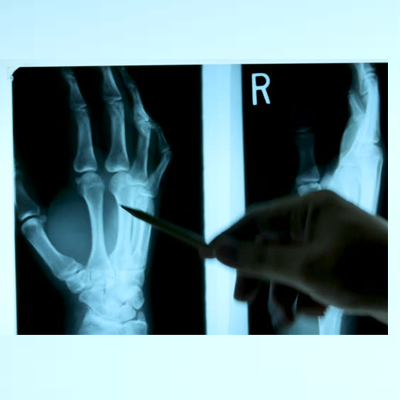

X-rays are primarily used in the medical and dental field. Some of the more common X-rays are done for broken bones and fractures, swallowed items, damage to bones from arthritis, and lung infections. X-rays are also used in a CT scanner, or computed tomography. This modality uses multiple X-rays during one scan, to give a layer-by-layer image. X-rays are also being used in non-medical areas, like airport security and by NASA in outer space.